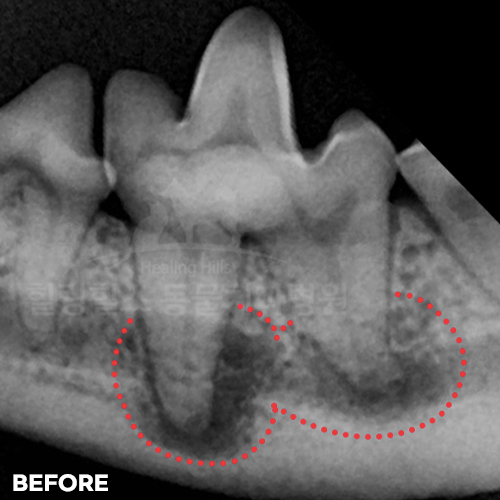

[강아지 잇몸에 고름] 최소침습적 발치 후 씨티로 확인된 자기잇몸뼈 증식! 치조골 살리는 힐링힐스 동물치과병원

2025.10.27